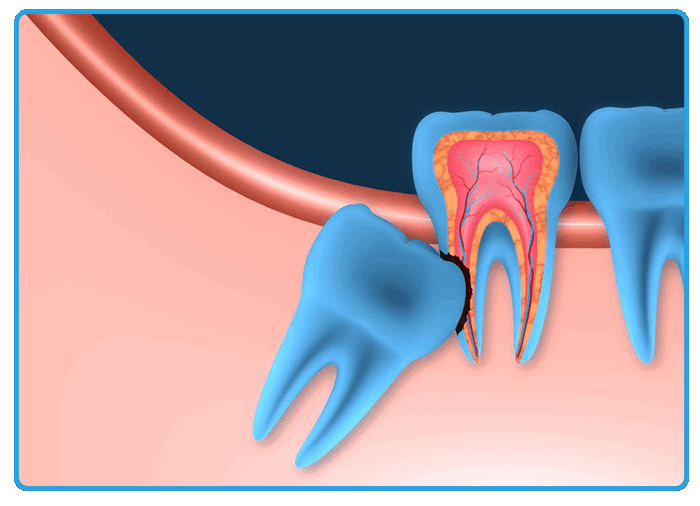

Тесное расположение ретинированных и сверхкомплектных зубов и корней соседних зубов может привести к их повреждению во время операции. Следствием этого может быть нарушение формирования корня, гибель ростковой зоны, некроз пульпы и развитие необратимых деформаций альвеолярного отростка с выраженным эстетическим недостатком (рис. 1, 2) .

Рис. 1. Последствия травмы корня зуба 1.1 при удалении сверхкомплектного зуба в возрасте 8 лет